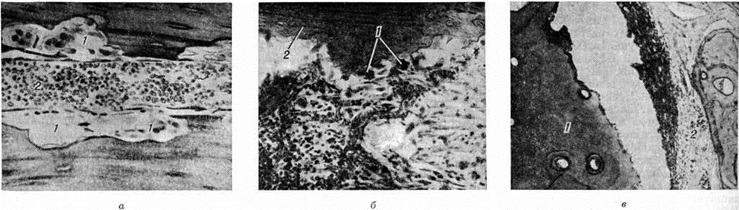

В других случаях наблюдается инкапсуляция гнойников в кости. К 3—4-й недель от начала заболевания при рентгенологическое исследовании на фоне рарефикации определяются очаги некроза кости, поскольку омертвевшая кость не подвергается резорбции и сохраняет прежнюю плотность. При патологоанатомическом исследовании участки некроза выявляются ещё раньше. В дальнейшем те из них, которые находятся в самом очаге нагноения, подвергаются секвестрации (рисунок 1). Секвестрация (смотри полный свод знаний Секвестр, секвестрация) заключается в отторжении омертвевших участков кости, находящихся в полости гнойника, от окружающей костной ткани. При этом в случае образования секвестра в компактной пластинке на её поверхности в зоне прилегания грануляций возникает и постепенно углубляется секвестральная борозда, а в толще — расширение гаверсовых каналов и слияние их между собой. После того как все костное вещество в указанной зоне растворится, секвестр оказывается свободно лежащим в полости гнойника (цветной рисунок 2 и 3). Секвестры губчатого вещества кости отделяются от остальной её части за счёт растворения прилежащих костных балок, находящихся в зоне грануляций (рисунок 2).

Секвестры препятствуют заживлению очага Остеомиелит Возможность «вживления» или рассасывания секвестра большинством исследователей отрицается, так как в его толще даже при обильном применении антибиотиков сохраняются микроорганизмы, подавляющие активность тканевых ферментов. В эксперименте как рассасывание, так и «вживление» секвестров наблюдаются лишь в условиях стерильного нагноения, например, после введения в кость кротонового масла.